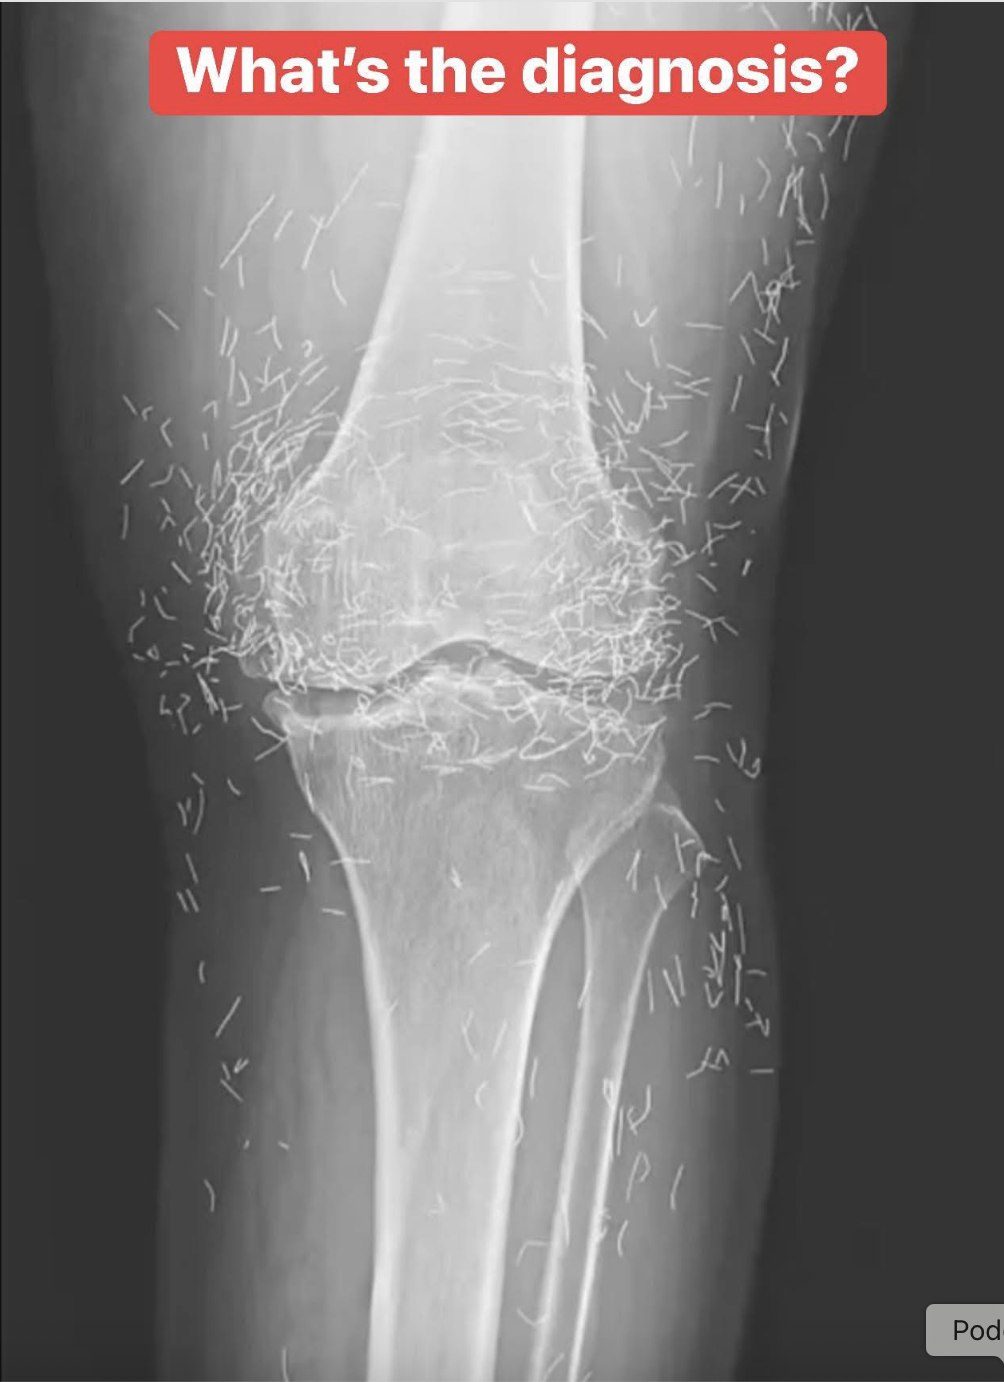

Acupuncture, an alternative treatment with a history spanning centuries, entails the insertion of needles into specific points on the body to alleviate pain or address various health issues. In this particular instance, the needles—likely crafted from gold—were deliberately left in her knees to provide ongoing stimulation.

He further cautioned that needles left embedded can interfere with X-ray interpretations. “The needles may obscure certain anatomical structures,” Guermazi remarked in 2013.

Even more troubling, needles that remain in the body can pose risks for future medical imaging. “The patient cannot undergo an MRI because needles left in the body might shift and injure an artery,” Guermazi noted.